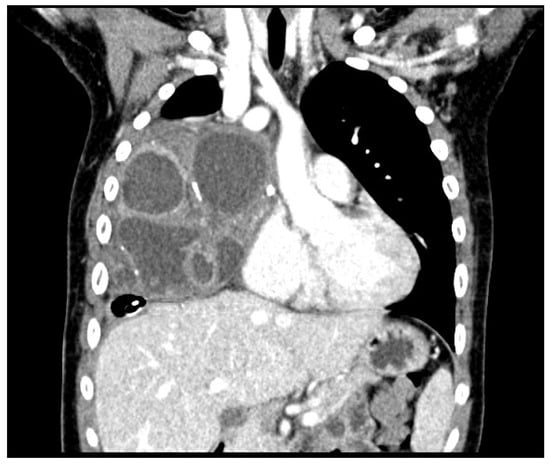

2. Case Report